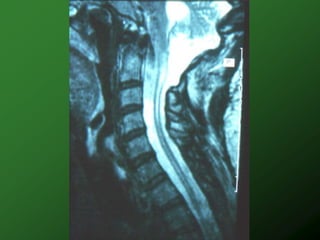

 Syringomyelia

Other Complications  Deep vein thrombosis lovenox 8-12wk, ASA  Gallstones  Pneumonia  Syringomyelia